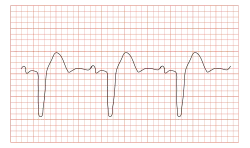

| ECG showing a bundle branch block | |

A bundle branch block can be diagnosed when the duration of the QRS complex on the ECG exceeds 120 ms. A right bundle branch block typically causes prolongation of the last part of the QRS complex and may shift the heart's electrical axis slightly to the right. The ECG will show a terminal R wave in lead V1 and a slurred S wave in lead I. Left bundle branch block widens the entire QRS, and in most cases shifts the heart's electrical axis to the left. The ECG will show a QS or rS complex in lead V1 and a monophasic R wave in lead I. Another normal finding with bundle branch block is appropriate T wave discordance. In other words, the T wave will be deflected opposite the terminal deflection of the QRS complex. Bundle branch block, especially left bundle branch block, can lead to cardiac dyssynchrony. The simultaneous occurrence of left and right bundle branch block leads to total AV block.

A simple way to quickly differentiate between the two types is to note the deflection of the QRS complex in the V1 lead. A (V1) QRS segment deflected down indicates left bundle branch block, while a deflection up indicates right bundle branch block. In both types, the QRS is wide (> 0.12 seconds).